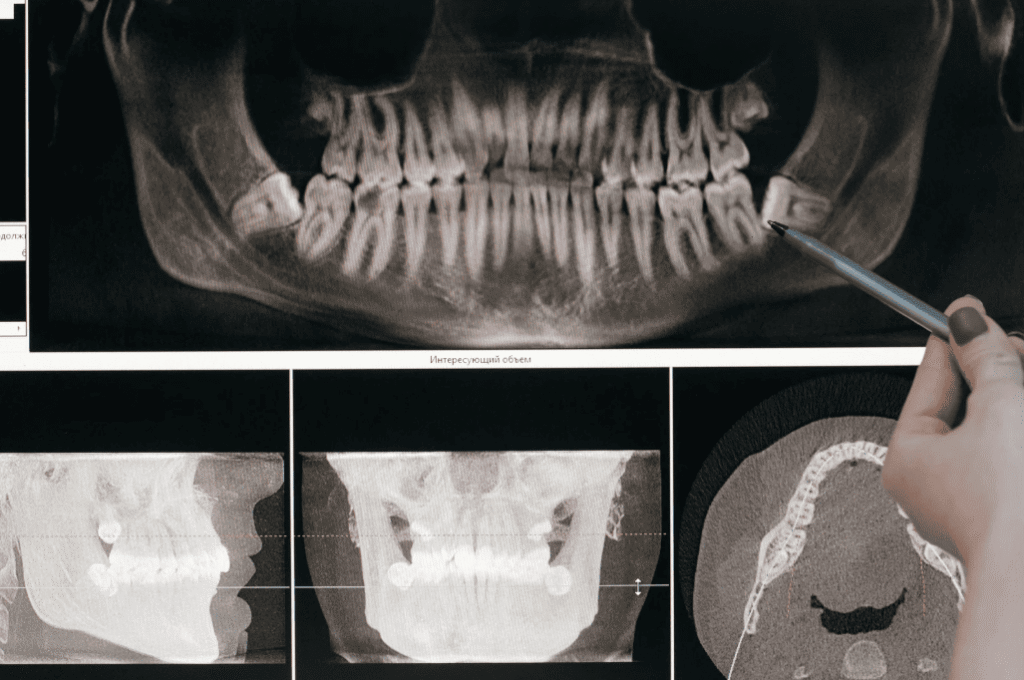

👉 Action: If you notice any of these symptoms, it is important to book a dental check-up promptly. A dentist can examine the extent of tooth wear, muscle tension, and TMJ (temporomandibular joint) function to assess whether you have sleep bruxism and recommend a personalized treatment plan.

✅ 5. Regular Dental Check-Ups

Even without obvious symptoms, it’s recommended to have a dental check-up every 6–12 months to:

- Monitor tooth wear

- Detect early cracks, loose restorations, or TMJ problems

- Allow your dentist to assess if a night guard or other treatment is needed